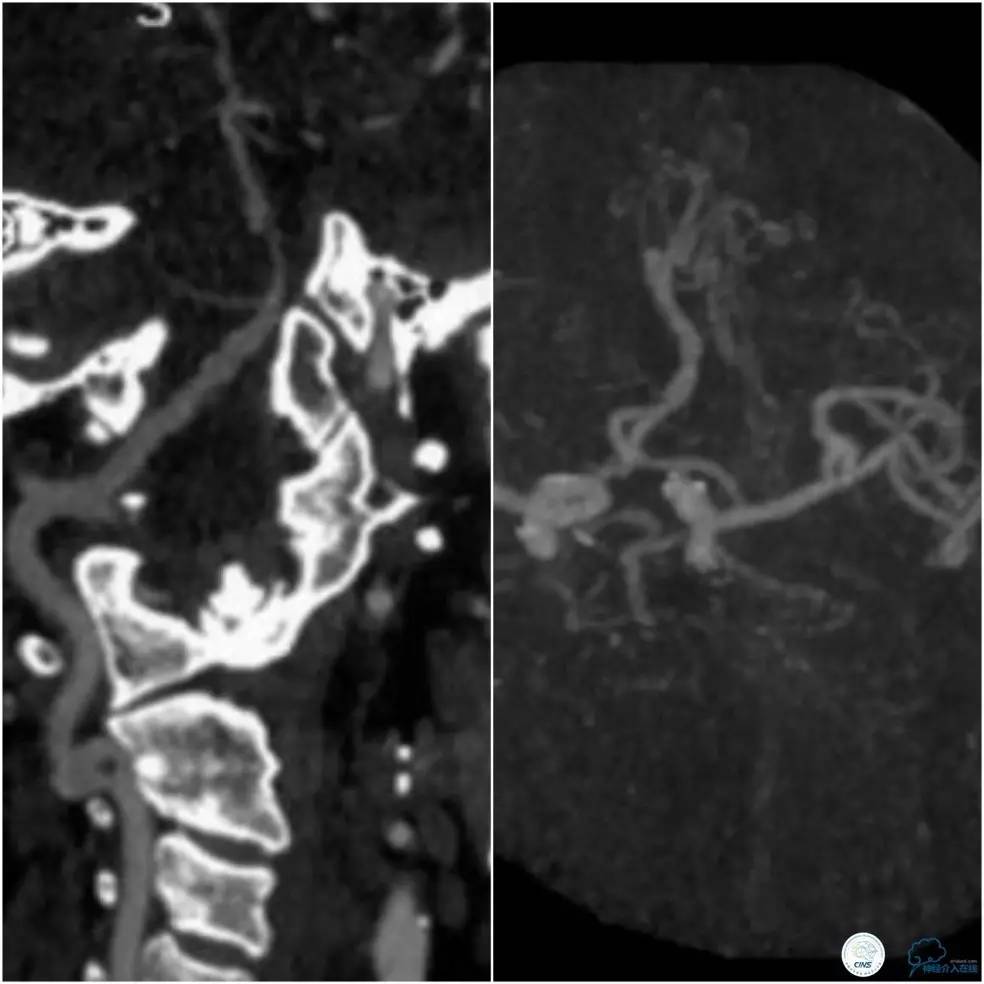

头颈部CTA示基底动脉及右侧椎动脉V4段狭窄,基底动脉狭窄远端局部管腔扩张(图2)。

图2

头颅CTA示(图5):右椎动脉优势、局部狭窄,左侧椎动脉细、狭窄;基底动脉迂曲,起始处狭窄,中部可见突起影。

图5